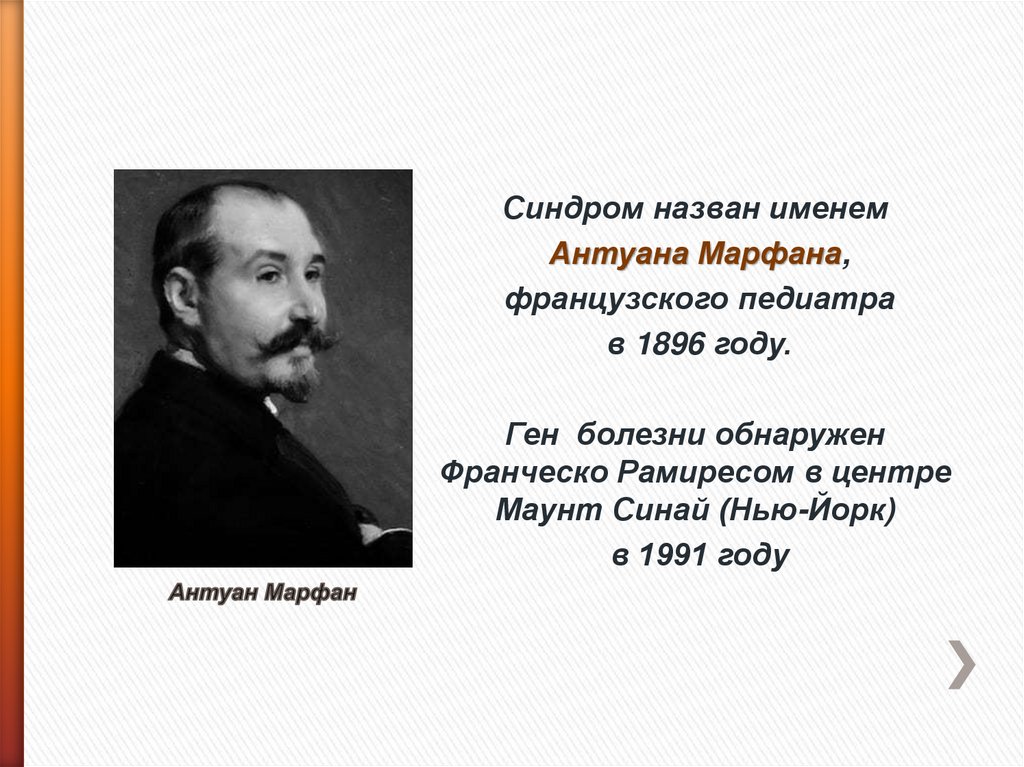

Sindrom marfana tema nauchnoj stati po klinicheskoj medicine chitajte besplatno tekst nauchno issledovatelskoj raboty v elektronnoj biblioteke kiberleninka (Тип файлу jpg)

Sindrom Marfana Tema Nauchnoj Stati Po Klinicheskoj Medicine Chitajte Besplatno Tekst Nauchno Issledovatelskoj Raboty V Elektronnoj Biblioteke Kiberleninka